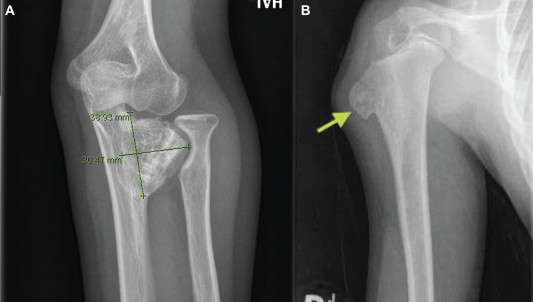

The Osteochondromas Treatment market is also influenced by advancements in medical imaging technology and surgical techniques. High-resolution imaging modalities, such as MRI and CT scans, enable accurate diagnosis and assessment of osteochondromas, aiding in treatment planning. Additionally, minimally invasive surgical approaches, including arthroscopic resection, are becoming more widely adopted due to their potential for reduced postoperative pain and quicker recovery times. These innovations are enhancing the overall patient experience and expanding the market for osteochondromas treatment options.